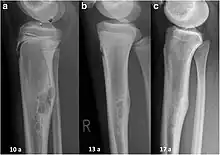

| Non-ossifying fibroma of tibia | |

The most common bone tumor is a non-ossifying fibroma.[4] Average five-year survival in the United States after being diagnosed with bone and joint cancer is 67%.[5] The earliest known bone tumor was an osteosarcoma in a foot bone discovered in South Africa, between 1.6 and 1.8 million years ago.[6]